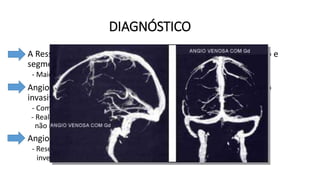

DIAGNÓSTICO

• A Ressonância Magnética é o exame de escolha para diagnóstico e

segmento da TVC.

- Maior detalhe do trombo e alterações teciduais.

• Angiotomografia e Angioressonância – Estudos venográficos não

invasivos.

- Complementam o estudo;

- Realizados em pacientes com suspeita de TVC, especialmente se a RM

não esclareceu o diagnóstico ou apresentou resultado falso-negativo.

• Angiografia cerebral por cateterismo.

- Reservada para os casos com diagnóstico inconclusivo após

investigação não invasiva.

Novas diretrizes:

- A confirmação do diagnóstico será por

Angiotomografia Venosa ou Angioressonância

Venosa de Crânio (Maior sensibilidade). Esses

exames demonstrarão falha de enchimento do

contraste na região acometida.